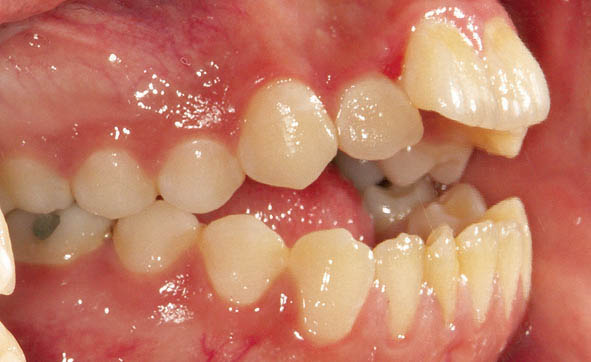

شکل 44-3

شکل 45-3

شکل 46-3

شکل 44-3 الی 46-3: اینترود خلفیها منجر به بسته شدن بایت بیمار میشود